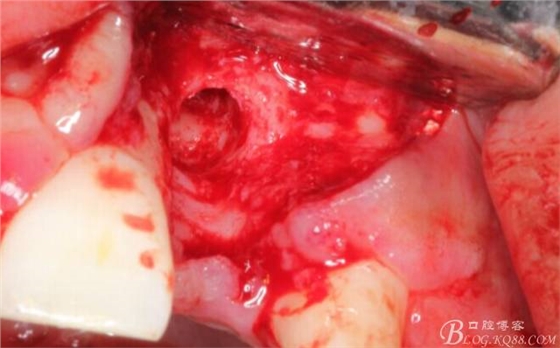

有老師問(wèn)我,為什么不在此時(shí)同期植骨同期植入植體?我的觀點(diǎn)是:不要一次做太多事情,做得越多風(fēng)險(xiǎn)越高。再說(shuō),此時(shí)軟組織不健康,沒(méi)有健康的軟組織如何能保證GBR的成功?所以,我僅放了一塊膠原蛋白就縫上了。